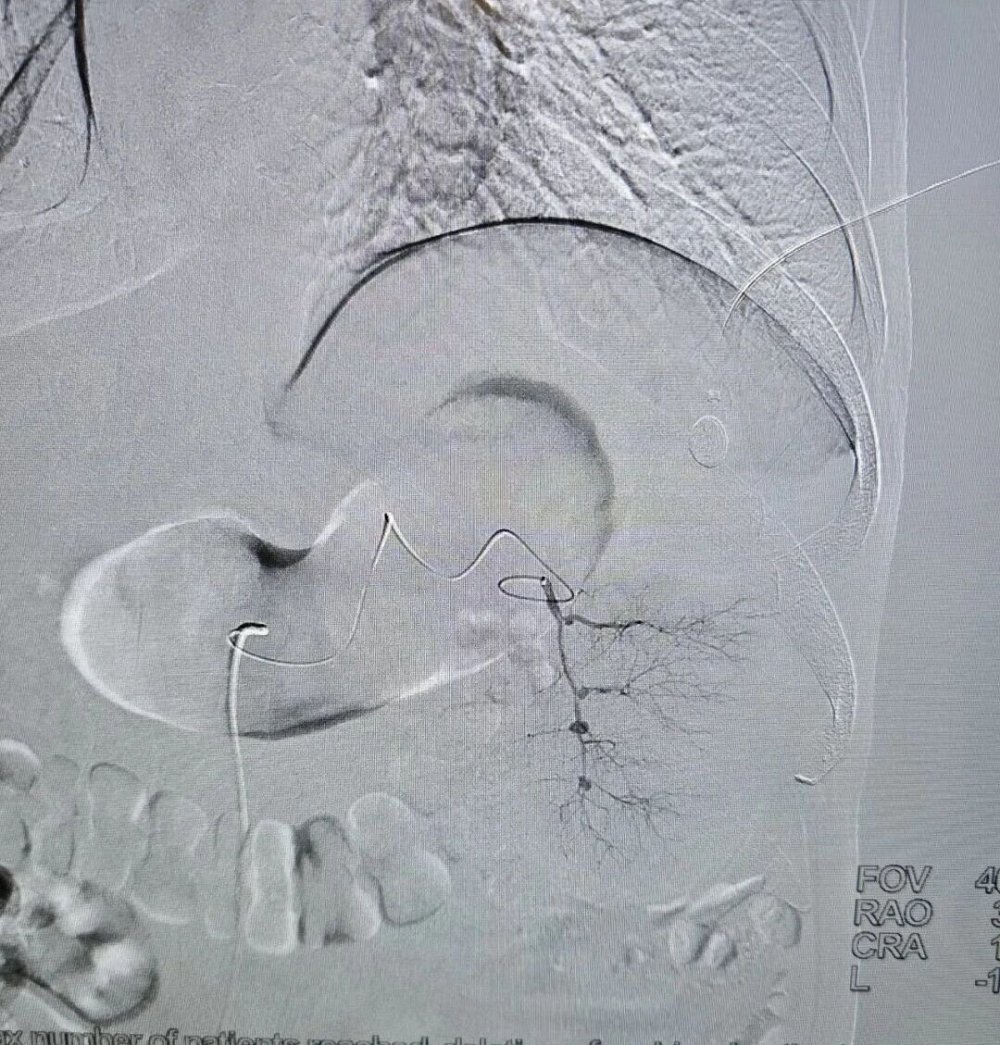

手术全程在数字减影血管造影(DSA)高清影像实时监控下开展,全程可视化操作,精准、安全、可控。

术中,介入医学科负责人卜高峰通过微细导管沿血管通路精准送达脾动脉主干,精准定位异常增生、过度亢进的病变脾组织血管分支,注入专用栓塞颗粒,选择性阻断脾脏病变区域血供,让亢进的脾组织逐步缺血萎缩,从根源解决脾功能亢进问题。

手术中,导管精准抵达脾动脉位置,清晰显示脾脏血管供血形态,为后续栓塞操作提供精准定位

栓塞过程中,通过导管向病变脾组织血管注入栓塞颗粒,精准阻断异常供血,最大程度保留正常脾组织。